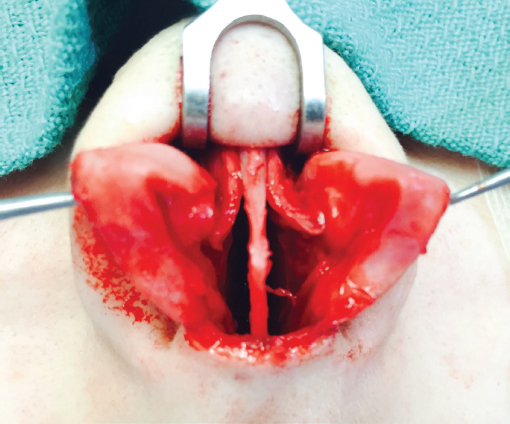

The transverse columellar incision is made initially with a no. 11 blade. It is joined with a vertical marginal incision made superficially, so as not to incise the underlying crus, beginning at the soft tissue triangle. The columellar flap is freed up with scissors dissection up to the angle. We prefer to carry blunt and sharp scissors dissection superolaterally over the dome and along the lower lateral crus, allowing exposure of the tip cartilages under direct vision. However, it is occasionally necessary to first make the marginal incision with retrograde exposure in cases of severe scarring or unusual lobular configurations that render scissors dissection over the domes precarious. Elevation of dorsal skin may be performed blindly as in the closed technique. In cases of severe scarring, poorly defined deformities, or thin skin, exposure is performed under direct vision with scissors or knife dissection. Bleeding from the inferior columellar artery or from branches of the facial artery in the region of the pyriform aperture may be controlled with conservative bipolar cautery. The dorsal skin is elevated in a submucoperichondrial and submucoperiosteal plane to diminish bleeding and tissue trauma. A balance is struck between maintenance of soft tissue support and skin elevation sufficient to allow appropriate surgical maneuvers and postoperative skin redraping.

Septoplasty is usually performed first to correct functional problems and to obtain any cartilage that may be necessary for grafting. The superior septal angle is easily identified, and soft tissue is removed from between the medial crura down to the premaxilla. This provides excellent exposure of the caudal septum and allows the columella to be narrowed. This is especially helpful if a columellar strut is to be placed because struts widen the columella inferiorly. If nasolabial augmentation is required, this soft tissue may be retained as a flap based inferiorly and turned on itself to provide additional nasolabial angle augmentation. 14 It is secured with a throughandthrough premaxillary transfixion suture. More frequently, the soft tissue is excised to be used later as a camouflage graft if required. We often deepen or flatten the premaxilla at this juncture with a rongeur. The wide exposure offered by the open approach is much superior to closed techniques for this purpose. The nasal spine may be flattened to create an optimal platform for a columellar strut, but its excision is highly inadvisable. Beginning at the anterior septal angle, complete submucoperichondrial and submucoperiosteal septal flaps are elevated bilaterally. The upper lateral cartilages are separated from the septum such that the nasal dorsum and septum are ouvert au ciel, or open to the sky. This affords a superb undistorted view unavailable with closed techniques, allowing any desired septoplasty technique to be executed ( Fig. 34.9 ). Of note, the view is more anterosuperior than that seen in closed techniques and may require some adjustment of orientation in the mind’s eye.